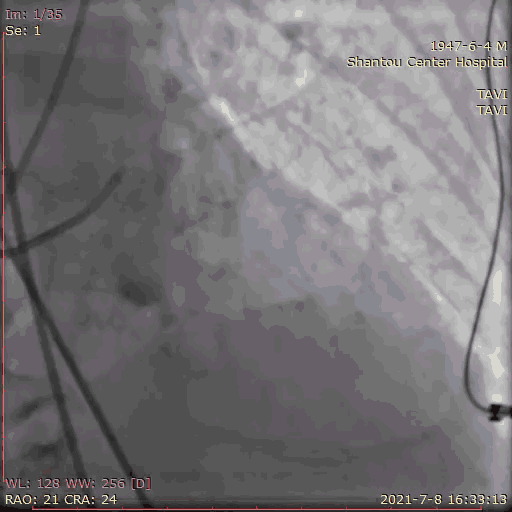

主动脉根部造影

临时起搏器植入后,辅入路穿刺,猪尾导管置于无冠窦底进行主动脉根部造影。

初步判断释放体位是否合适。

观察瓣叶活动度、是否合并反流,有利于跨瓣。

左右冠通畅,存在一定反流,有一定耐受能力,球扩时,循环崩溃风险较小。

左冠窦瓣叶活动度高、无钙化,无冠窦右冠窦活动度减轻,且钙化集中在基底部,右冠风险较左冠低。